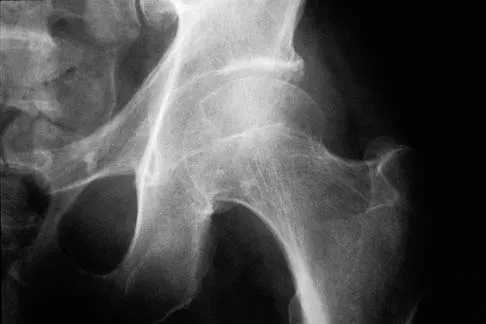

A 53-year-old patient is seen in the emergency department after sustaining a fall onto her left hip. A current radiograph is shown in Figure 40. What is the best treatment option?

Explanation